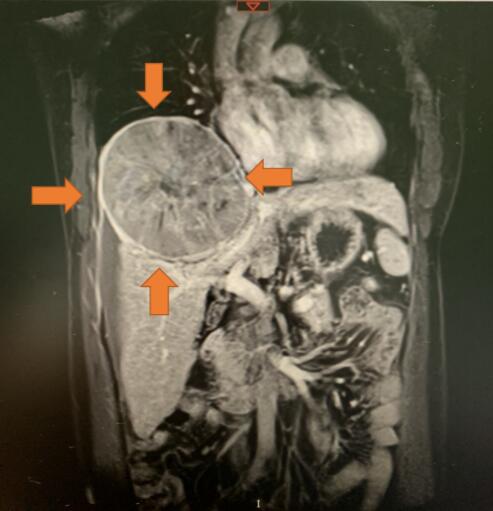

在4月底的一個深夜,韋先生突然被腹部的一陣劇痛驚醒,一家人急忙來到醫院就診,初步檢查發現肚子裏面竟然從肝臟長出一個巨大的腫瘤,經過第二天的CT檢查進一步確認了病情,腫瘤直徑大約15cm,就像一個小皮球那麼大,同時腫瘤向上生長擠壓右側的肺部,更糟糕的是由於腫瘤太大已經有破裂出血,如果再不及時治療可能就會有生命危險。

經過一系列檢查,患者各項指標滿足手術條件,而且腫瘤沒有轉移到其他部位。吳凡介紹說,患者的腫瘤長在肝臟的中心部位,屬於手術難度較高的中央型肝癌,這種手術既要完整切除腫瘤又不能損傷通往肝臟左側及右側的管道系統。因為一旦損傷,患者的肝臟將遭到不可逆轉的影響,甚至因為肝功能衰竭導致死亡。